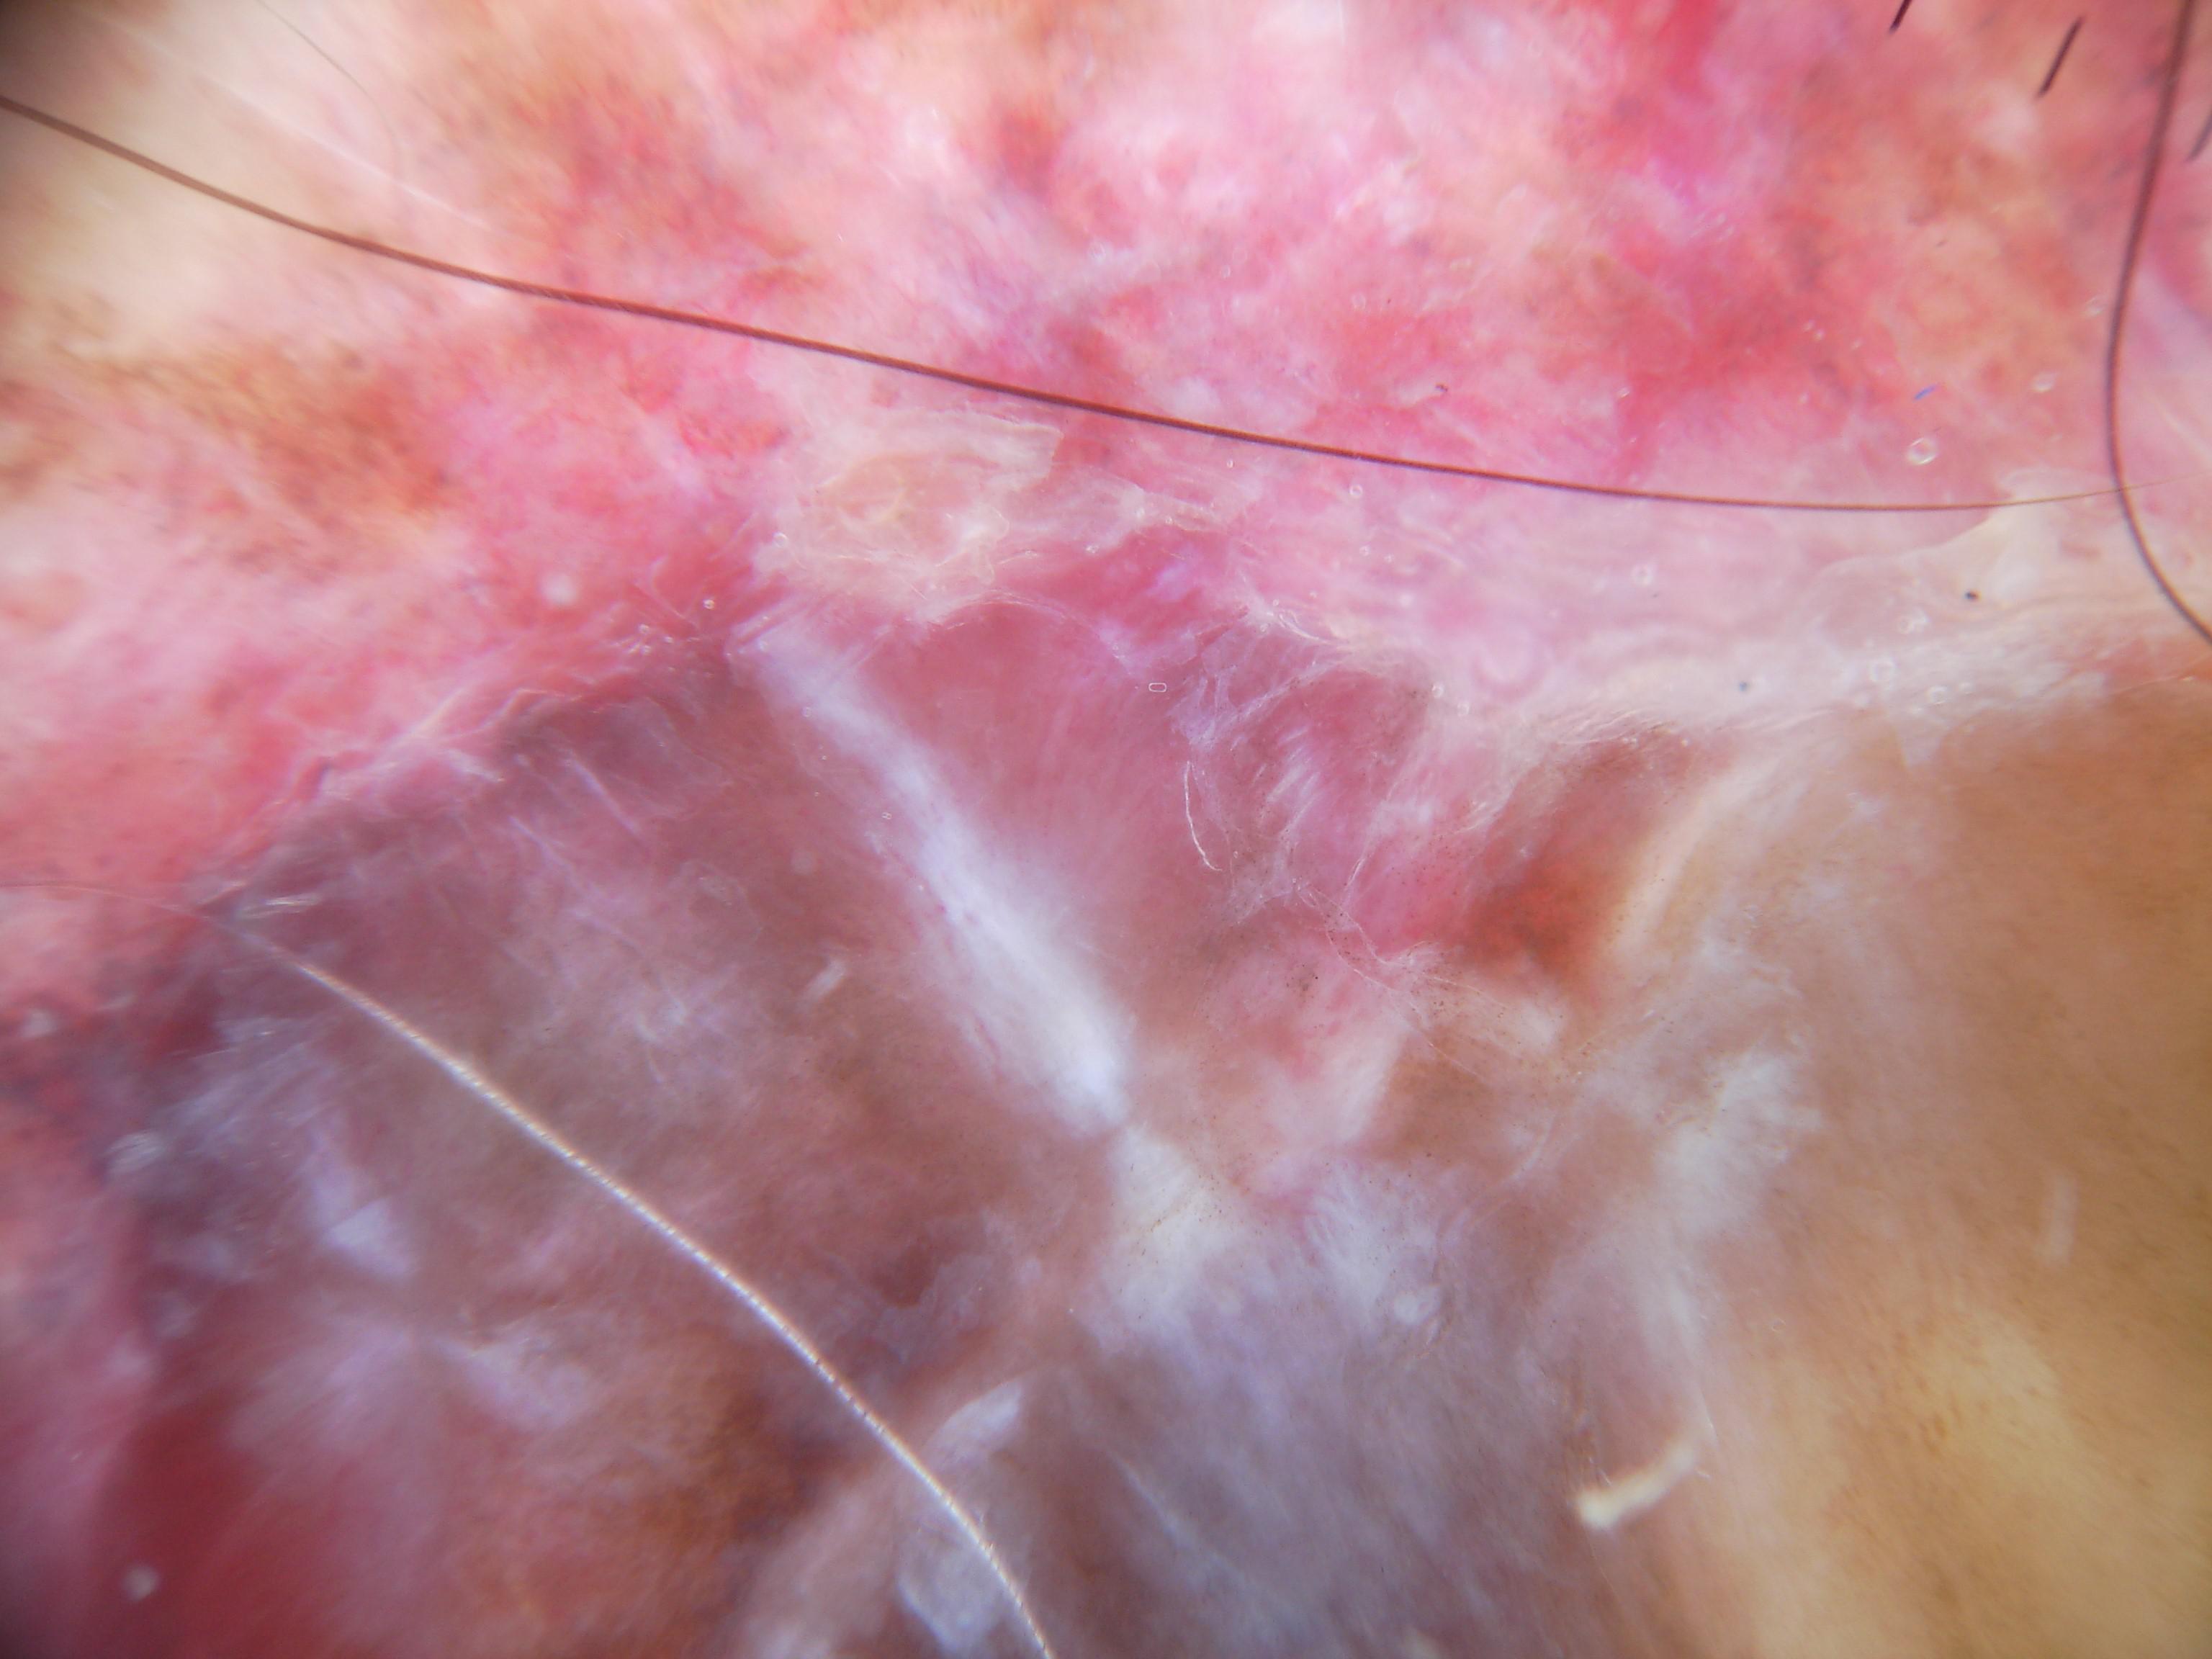

{

"age_approx": 85,

"anatom_site_general": "upper extremity",

"concomitant_biopsy": true,

"dermoscopic_type": "contact polarized",

"diagnosis_1": "Malignant",

"diagnosis_2": "Malignant melanocytic proliferations (Melanoma)",

"diagnosis_3": "Melanoma Invasive",

"diagnosis_confirm_type": "histopathology",

"family_hx_mm": false,

"image_type": "dermoscopic",

"mel_thick_mm": "4.30",

"melanocytic": true,

"patient_id": "IP_0126628",

"personal_hx_mm": false,

"sex": "male"

}